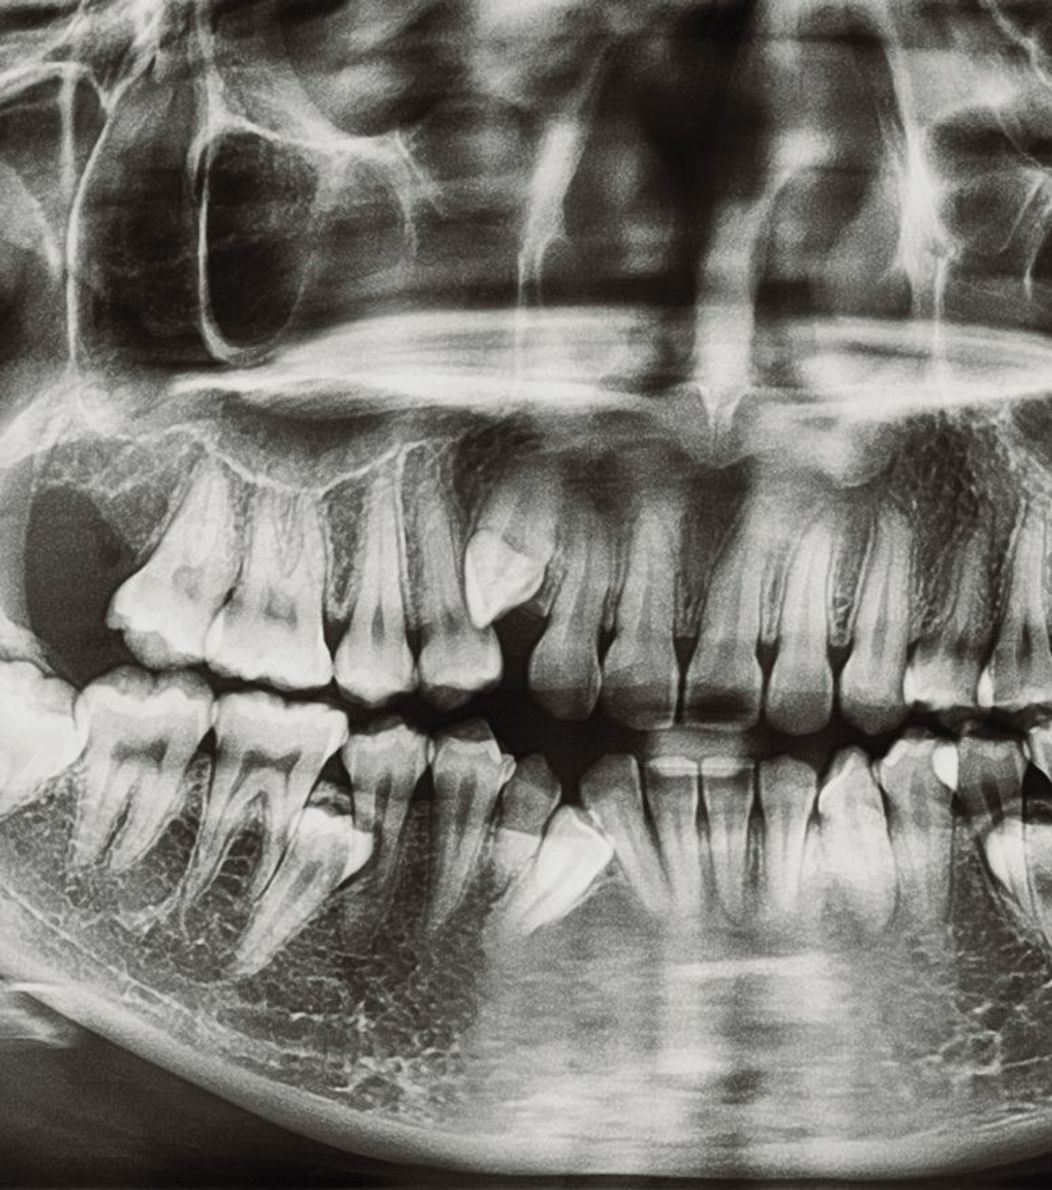

Dental implants restore your entire tooth, from root to crown, by being inserted directly into the socket. To maintain the bone's strength and health and to firmly anchor your new tooth in place, they fuse with the jaw. Implants are durable and frequently maintain their perfect state for a lifetime.